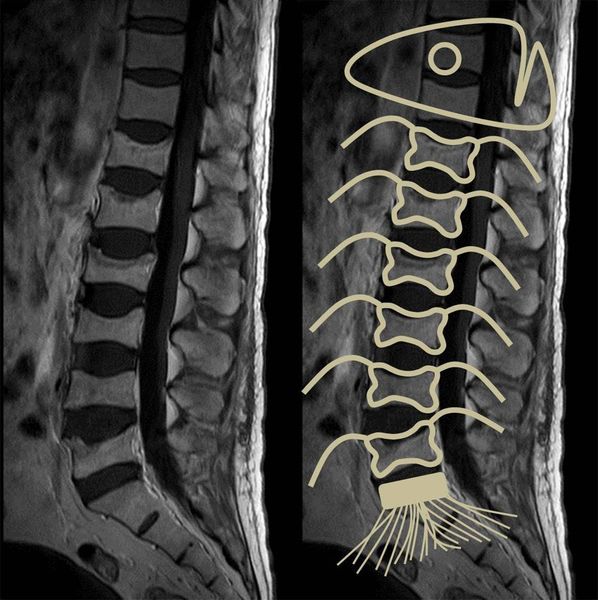

- спина бифида — незаращение дужек позвонков, которое сопровождается неврологическими нарушениями (зачастую — слабостью и параличом ног, нарушением мочеиспускания и дефекации); по мере развития заболевания через открытое отверстие в позвоночнике выпячивается спинной мозг и его оболочки (миеломенингоцеле), при этом чем выше располагается выпячивание, тем тяжелее симптомы [3].

Спина бифида